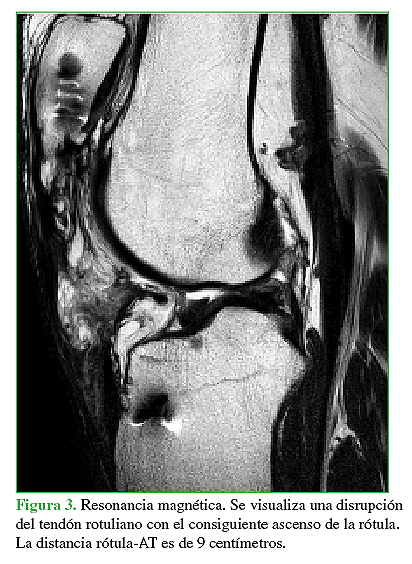

La rotura primaria del tendón rotuliano es una patología poco frecuente que afecta principalmente a adultos activos jóvenes. Aún menos frecuente, es la rotura crónica o recurrente del tendón rotuliano, y es esta última situación, la que presenta una importante dificultad técnica a la hora de realizar el debido tratamiento quirúrgico. El objetivo de este trabajo es la presentación de un caso donde se realizó la reconstrucción quirúrgica del aparato extensor mediante la utilización de aloinjerto luego de haber presentado tres cirugías fallidas para la reparación del tendón rotuliano tras sufrir una lesión traumática del mismo. Se describe tanto la técnica quirúrgica como también el protocolo de rehabilitación.Descargas